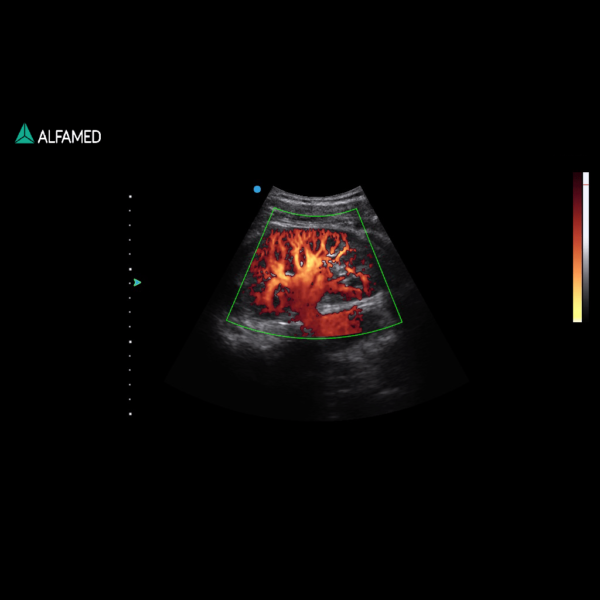

⦁ Microflow – Visualização de Micro vasos / Micro vascularização

⦁ MFI (Macro Fidelity Imaging)

⦁ Modo B, 2B, 4B, M, Power Doppler Direcional, CW, M, PW; B/M, CFM, B/C,

PWD, CPA, DPA, B+CFM, B+CPA, B+DPA, B+PW, B+CFM+PW, B+CPA+PW,

Triplex/Duplex;